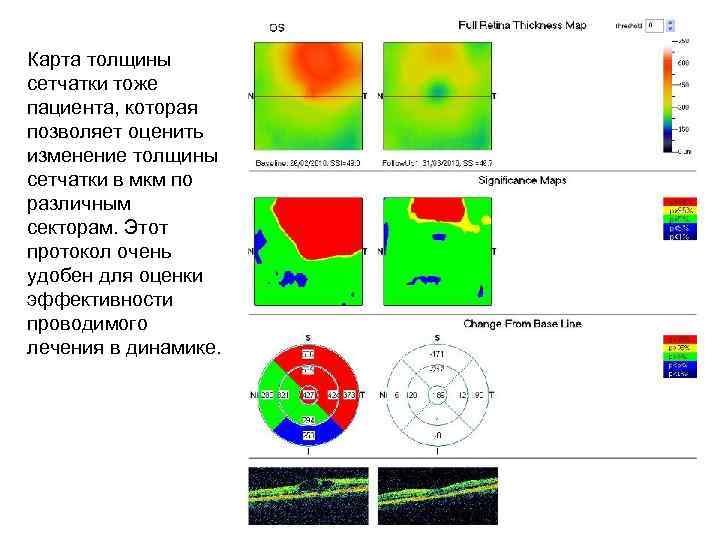

Диагностика зрения: Когерентная томография сетчатки

Раздел: Фотоальбом решений